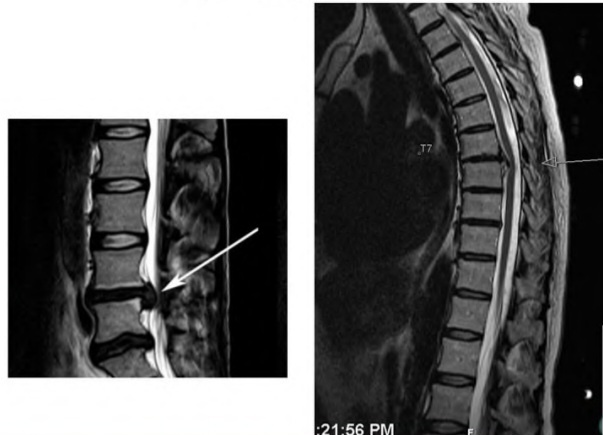

👇Грыжа диска - это ситуация, когда из-за нехватки воды, диск начинает разрушаться, и в зависимости от того какой образ жизни Вы ведете в том месте остатки этого диска и скапливаются

То что там по счастливой случайности нашли грыжу, протрузию, или ещё чего, является следствием длительной потери питания (воды) диском.

🗒БОЛЕВОЙ СИНДРОМ НИКАК НЕ КОРРЕЛИРУЕТ НИ С НАЛИЧИЕМ ГРЫЖИ, НИ С ЕЁ РАЗМЕРАМИ

🦵С таким же успехом Вы бы могли сделать Рентген за год до болевого синдрома и увидеть там свои разрушенные 4, 6, 8 мм...

То же самое и наоборот, Вы можете страдать и мучатся от боли, а на Рентгене/МРТ никаких проблем и не увидеть